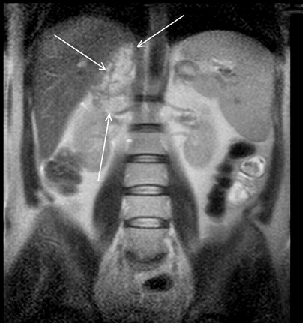

Рисунок 9. МРТ (фронтальная проекция) — опухоль правого надпочечника

Основные достоинства МРТ — неинвазивность, безвредность, трехмерный характер получения изображений. Однако этот метод является одним из самых дорогостоящих, и о применении МРТ при опухолях надпочечников существуют разноречивые мнения. По мнению Nakao Y.et al. (1993), МРТ перспективна для выявления опухолей малых размеров, а Н. Лавин (Эндокринология, 1999) считает, что МРТ в некоторых случаях дополняет результаты КТ, но при малых размерах опухоли надпочечника чувствительность этого метода не превышает чувствительности КТ. Однако, несмотря на использование различных инструментальных методов, точный диагноз, особенно при гормонально-неактивных опухолях, позволяет установить лишь морфологическое исследование, которое возможно при исследовании материала, полученного при аспирационной тонкоигольной биопсии под контролем УЗИ или КТ (Giron J., 1997; Petronio R., 1985) (рис. 10). Точность метода равняется 80–90% (Gonczi I. et al., 1987).

Рисунок 10. Тонкоигольная пункция опухоли (адренокортикальный рак) левого надпочечника под контролем КТ

Однако при гормонально-активных опухолях выполнение биопсии чревато развитием криза (Хитрова А.Н., 1996).